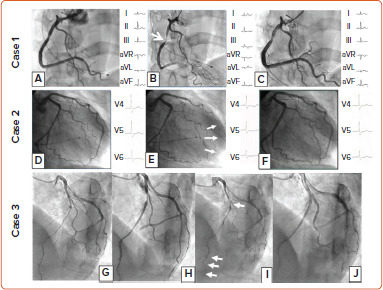

血管活性测试被心脏病专家用于诊断冠状动脉痉挛内型,如心外膜和微血管痉挛。根据冠状动脉血管运动障碍(COVADIS)小组的定义,冠状动脉内注射乙酰胆碱和麦角新碱是标准的一级方法。由于单一血管反应性检测在发现冠状动脉痉挛方面可能存在一些临床局限性,因此应重新考虑辅助性或顺序性血管反应性检测。大多数心脏病专家在进行这些血管反应性检测时不会考虑假阴性结果。在记录临床痉挛时,血管反应性检测可能存在一些局限性。今后,世界各地的心脏病专家应在心导管实验室使用多种血管反应性测试来验证心外膜和微血管痉挛的存在与否。

Vasoreactivity testing is used by cardiologists in the diagnosis of coronary spasm endotypes, such as epicardial and microvascular spasm. Intracoronary injection of acetylcholine and ergonovine is defined as a standard class I method according to the Coronary Vasomotion Disorder (COVADIS) Group. Because single vasoreactivity testing may have some clinical limitations in detecting the presence of coronary spasm, supplementary or sequential vasoreactivity testing should be reconsidered. The majority of cardiologists do not consider pseudonegative results when performing these vasoreactivity tests. Vasoreactivity testing may have some limitations when it comes to documenting clinical spasm. In the future, cardiologists around the world should use multiple vasoreactivity tests to verify the presence or absence of epicardial and microvascular spasms in the cardiac catheterisation laboratory.